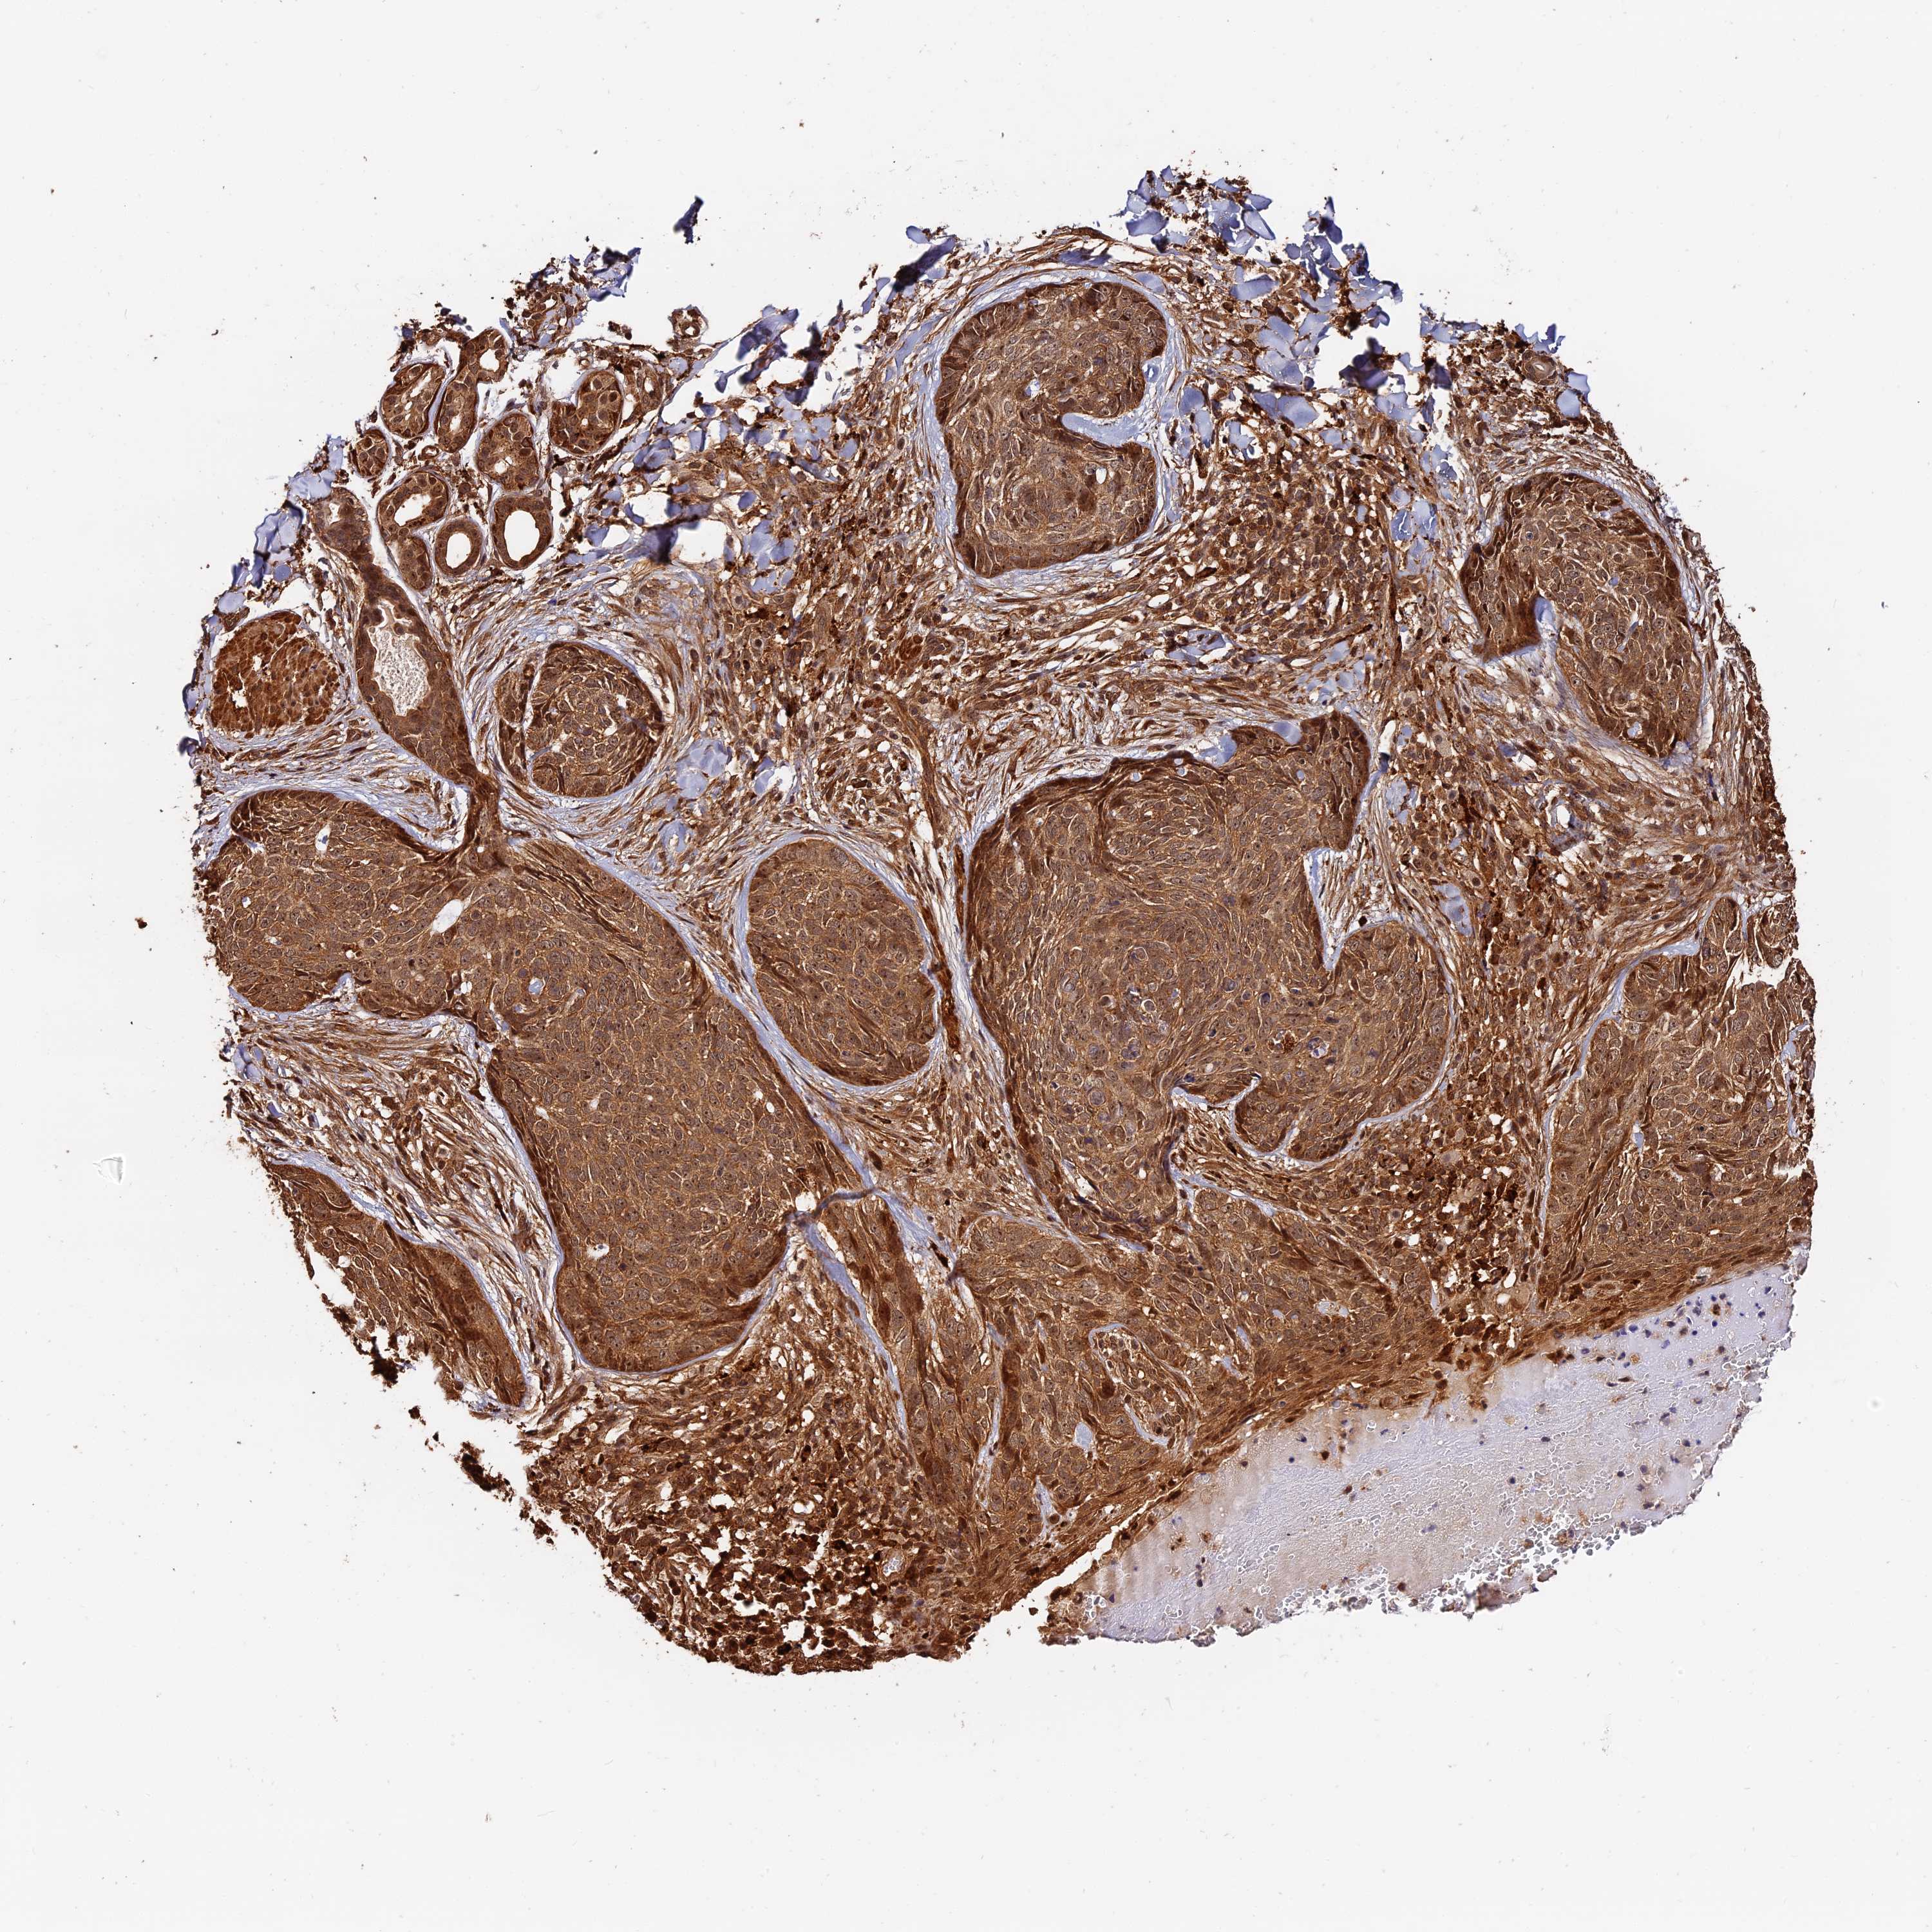

Basal cell and squamous cell cancer

SKIN CANCER - Protein expressioni

A mouse-over function shows sample information and annotation data. Click on an image to view it in a full screen mode. Samples can be filtered based on level of antibody staining by selecting one or several of the following categories: high, medium, low and not detected. The assay and annotation is described here.

Antibody stainingi

Antibody staining in the annotated cell types in the current human tissue is reported as not detected, low, medium, or high, based on conventional immunohistochemistry profiling in selected tissues. This score is based on the combination of the staining intensity and fraction of stained cells.

Each image is clickable and will lead to virtual microscopy that enables deeper exploration of all samples and also displays staining intensity scores, fraction scores and subcellular localization as well as patient and tissue information for each sample.

Antibody HPA040390

Antibody CAB002611

Squamous cell carcinoma, NOS